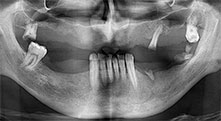

Bratu: Utilizamos los insertos de forma rutinaria para la extracción de injertos óseos y la ranuración de las crestas alveolares. También utilizamos las Piezomed B6/B7 para practicar osteotomías en dientes retenidos y no retiramos implantes que pueden conservarse. Todas estas son indicaciones que requieren cortes profundos y limpios.

Bratu: Preferimos realizar las osteotomías en la línea oblicua externa de la cara posterior del maxilar inferior, y no en la región situada entre los orificios. Tras realizar una incisión en los tejidos blandos, utilizamos las nuevas sierras para definir el contorno de la osteotomía. De este modo, conseguimos una preparación completa en prácticamente el 80 por ciento de los casos. Por otro lado, en algunas ocasiones también utilizamos otros insertos piezoquirúrgicos, así como un cincel para mover el injerto. Para nosotros, esta es una técnica de intervención muy eficaz.